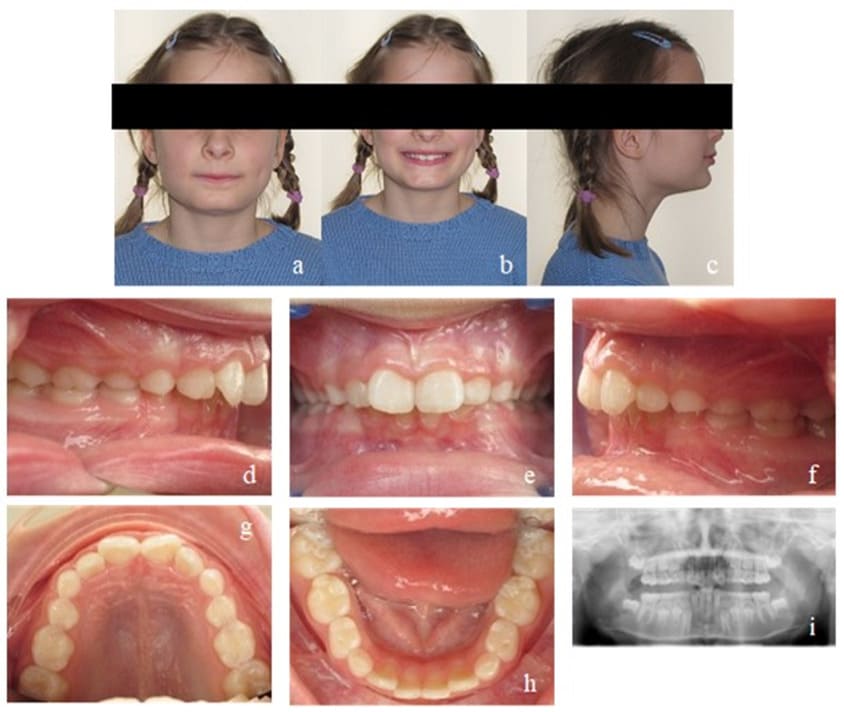

During her first appointment in our orthodontic office, this 8-year-old girl showed an age-appropriate mixed dentition, a bilateral mandibular retrognathism, an increased overjet of 7mm, an increased overbite of up to 80%, moderate crowding in the upper and mild crowding in the lower jaw. Myofunctional, an open mouth resting posture was observed (also described as lip incompetence) which led - in combination with the aforementioned increased overjet - to a resting position of the lower lip behind the maxillary incisors, favoring a large overjet. There were no speech impediments to be diagnosed but during swallowing, activation of the M. orbicularis oris and M. mentalis was observed. The lingual frenulum was short, her body posture normal (Figure 5). The defined orthodontic goals included the overjet and overbite reduction, mandibular advancement as well as elimination of crowding in both jaws. The myofunctional goals were the establishment of a habitual closed-lip position and nasal breathing to provide negative pressure in the oral cavity in order to ensure a physiological resting position of the tongue on the palate.

Orthodontic treatment was performed by using an EGA, chosen according to the occlusal factors and growth deficits of the jaws. Control intervals took place once a month. Directly following every orthodontic control, the patient received myofunctional therapy in the orthodontic office conducted by a specialized myofunctional therapist. After only six months, significant improvements, in both, the occlusal and myofunctional situation could be observed (Figure 6): the overjet was reduced to 3.5 mm, bringing the mandible forward by around ½ of a premolar width. In addition, there was an overbite reduction to 30%, while crowding in both jaws had almost completely been resolved. Due to the EGA and the lip closure exercises, the patient broke the habit of resting her lower lip behind her maxillary front teeth. Nasal breathing had been established in most situations except during physical exertion. The resting position of the tongue and its strength still needed further improvement.

Figure 5: Case 1. Initial findings. En face (a, b) and profile of the patient (c). Frontal view of the occlusion (e), occlusion right (d) and left (f). Upper (g) and lower arch (h). Initial Panoramic x-ray (i).